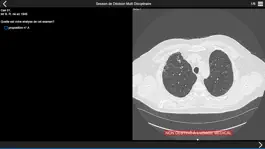

Consultez les examens tomodensitométriques des cas cliniques de pneumopathie infiltrante présentés lors de la session de discussion multidisciplinaire qui aura lieu dans la première partie de l'après-midi.